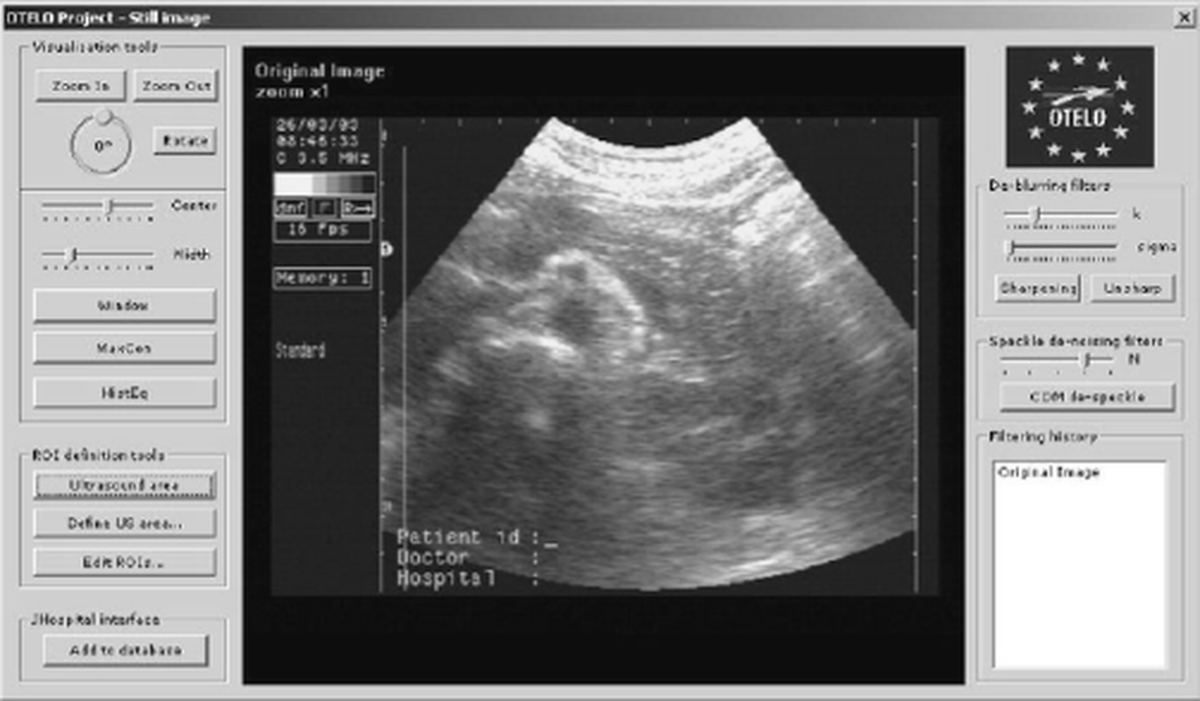

Mobile interconnectivity and telemedicine are important issues for achieving effectiveness in health care, since medical information can be transmitted faster and physicians can make diagnoses and treatment decisions faster. In this context, the OTELO project (OTELO, 2001) aims to develop a fully integrated end-to-end mobile tele-echography system using an ultra light, remote-controlled robot, for population groups that are not served locally by medical experts. An expert located in the expert center will do the echographic diagnosis. There will be only a "non-sonographer" person in the isolated site and the wireless transmission system will be the only link between the two sites. At the master station site, the clinical expert's role is to control and tele-operate the distant robot by holding a fictive probe.